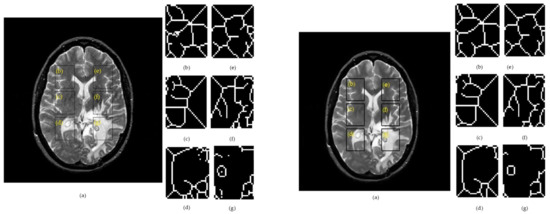

The flow chart of post-processing and analysis is shown in Figure 1.

The following steps were performed:

• Two datasets are generated: D1 contains raw images and D2 contains denoised images by using an anisotropic diffusion filter,

• select ROIs for further image manipulation tasks; insert and crop out the rectangle ROIs with a size of 35 × 45 pixels. This consisted of:

(i)

design the first rectangle mask in the right hemisphere,

(ii)

determine the distances to generate the other two rectangle masks in the right hemisphere,

(iii)

insert the other two masks into the right hemisphere according to the distances from step (ii),

(iv)

perform the mirror reflection of the masks into the right hemisphere onto the left hemisphere.

• crop out ROIs from both hemispheres, following the algorithm of step (II),

• compute SSIM for monochrome ROIs,

• segment ROIs with the skeleton algorithm,

• calculate S-Jaccard for ROIs processed in step (V),

• carry out a k-means clustering over SSIM and S-Jaccard values and pathologies,

• carry out cluster analysis with the silhouette method.

• carry out classification data using ROC analysis.

Both metrics (i.e., SSIM and S-Jaccard) were computed in every possible pair pathology-image type. For each dataset, 264 pairs were analyzed which belong to ROIs having the same spatial coordinates for all the studied images.

Figure 1. The proposed post-processing and analysis.